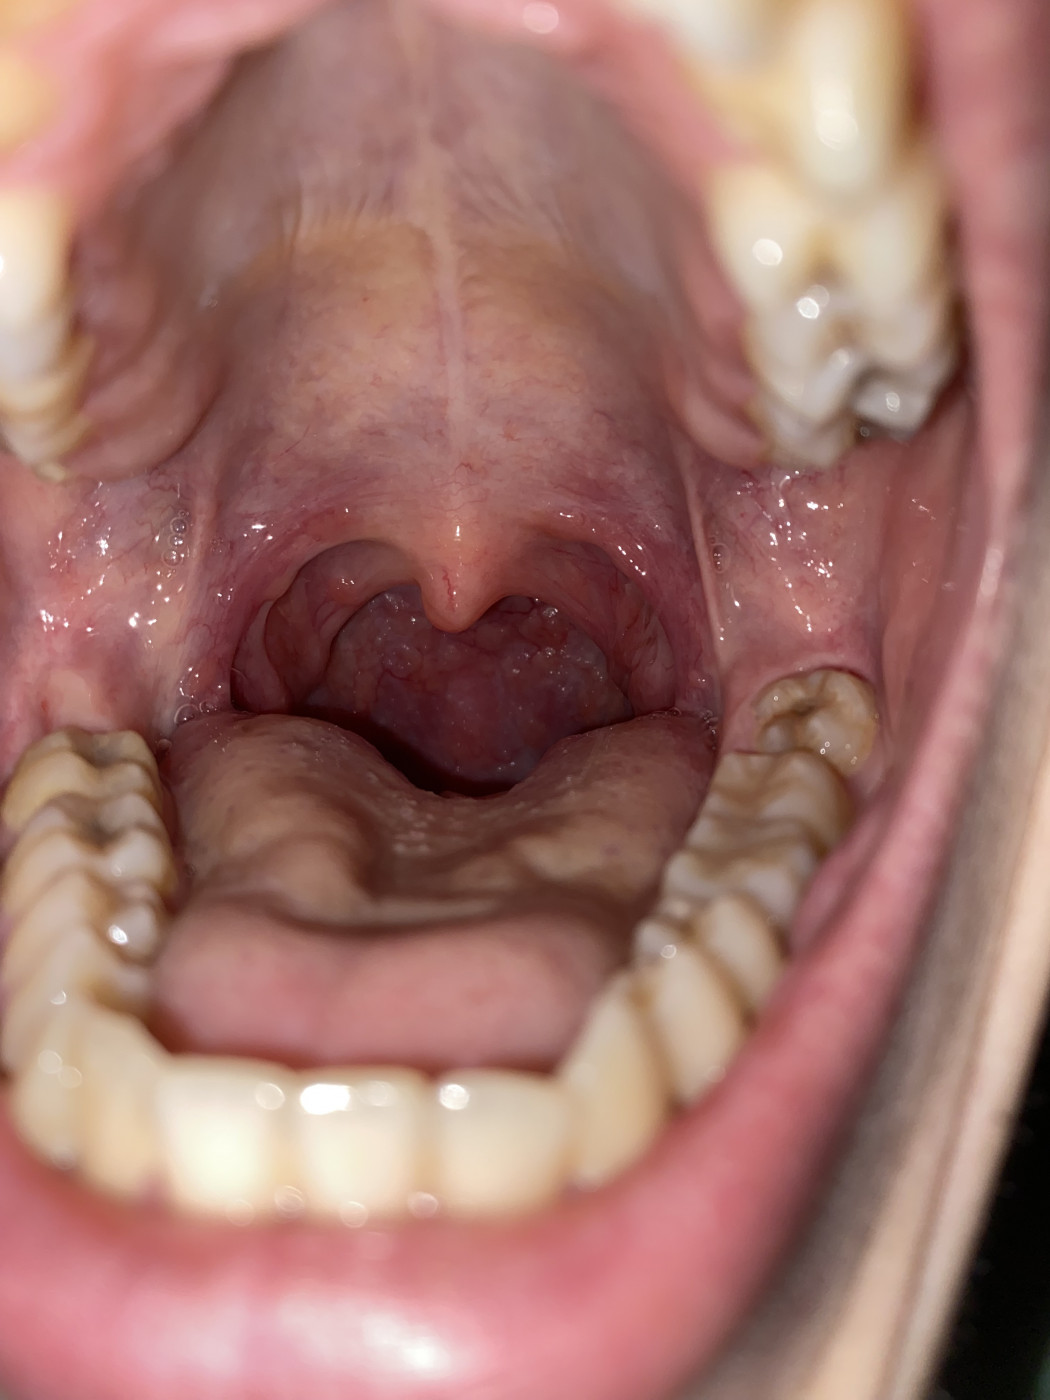

Тонзиллит

Какие бывают разновидности ангины и как их эффективнее всего лечить? Тонзиллит Острые респираторные заболевания, в число которых также входят острая и хроническая формы тонзиллита, широко представлены среди детей и взрослых даже несмотря на современный …